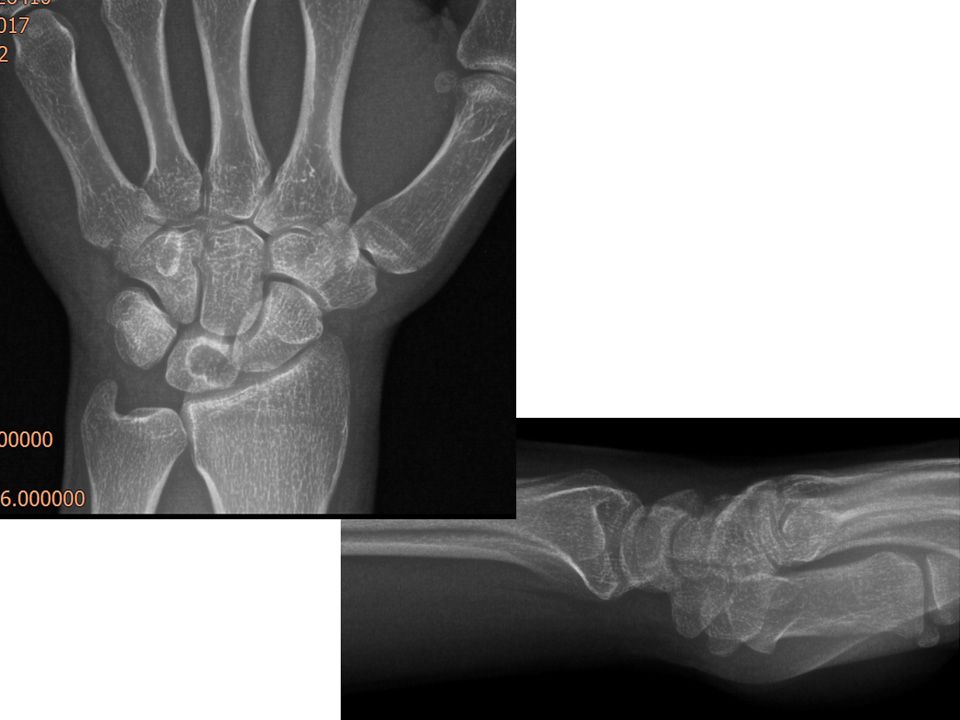

22 yaş, kadın, ev hanımı, sağ el dominant2 yıl önce düşme sonrası sağ el bileği dorsal ağrısıFTR, istirahat ateli ve NSAID’e rağmen geçmemişParmak ekstansiyon testi +